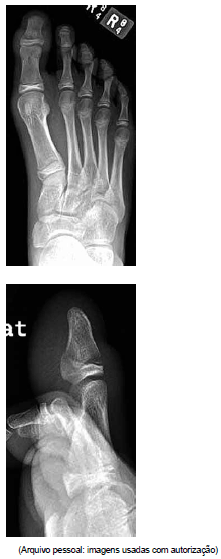

Menino de 13 anos sofreu fratura do dedo do pé, e optou-se por tratamento conservador. Alguns dias após, ele evoluiu com edema de partes moles e hematoma subungueal.

A radiografia realizada é mostrada a seguir.

Com base nos achados clínicos e nas radiografias, a complicação potencial mais provável para a qual o paciente tem risco é: